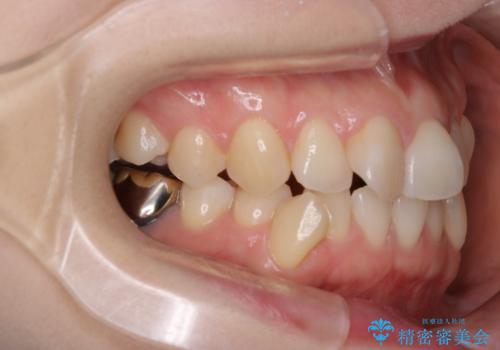

- 前歯の翼状捻転の改善を希望してこられた患者様です。

下顎の叢生はインビザラインで解決することがきましたが、上顎の捻転が完全には改善できなかったため、上顎は途中からワイヤーを用いて治療を行っています。